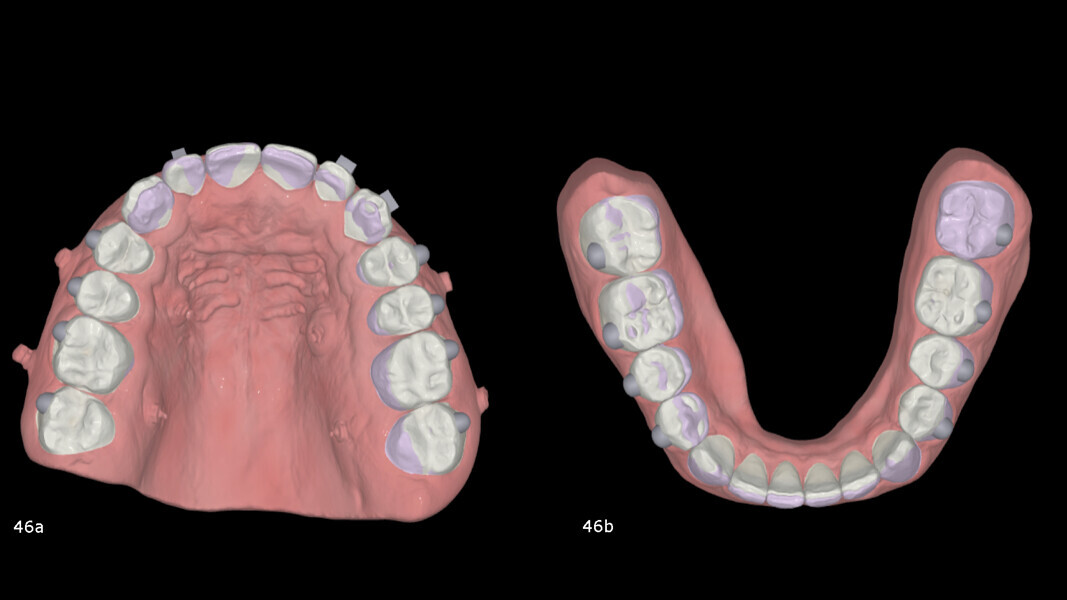

Once the bite had closed, treatment continued with aligners in both arches. The goals at this stage were to apply positive torque to the maxillary incisors and canines and to slightly retract the mandibular incisors, as well as to use IPR to improve the overjet and achieve ideal posterior intercuspation (Fig. 46). A total of ten maxillary and mandibular aligners were planned, followed by an additional refinement phase with another ten aligners per arch for finishing and detailing. The total treatment time, including the initial splint therapy, was 17 months.